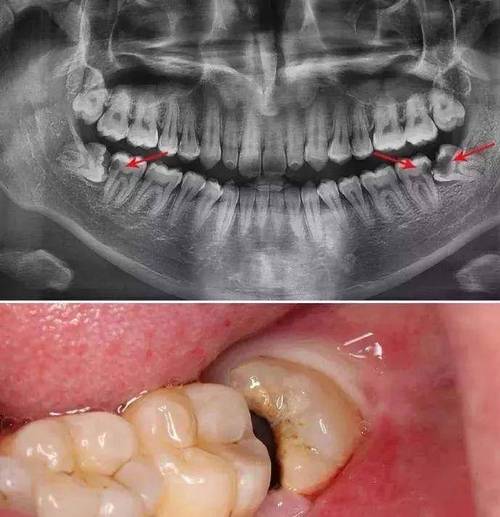

哭哭,我的智齿太靠近神经管了怎么办

智齿紧贴神经该怎么办上篇

下颌智齿离下牙槽神经管越近,难度也越大.

阻生智齿该不该拔

阻生智齿图片